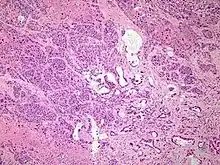

| Micrograph of an adenosquamous carcinoma of the lung. The adeno- or glandular component is on the left of the image and the squamous component on the right of the image. H&E stain. | |

Light microscopy shows a combination of gland-like cells and squamous epithelial cells.[4] On immunohistochemistry, it is typically positive for CK5/6, CK7 and p63, and negative for CK20, p16 and p53. On genetic testing, KRAS and p53 are typically altered.[4]